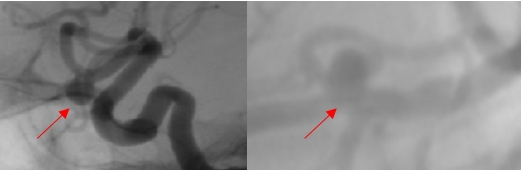

圖二:真實(shí)還原血管三維結(jié)構(gòu)—?jiǎng)用}瘤瘤頸曲面分割—微導(dǎo)管智能塑形方案。綠色為塑形針形態(tài),藍(lán)色為微導(dǎo)管形態(tài)。

AI軟件能夠精準(zhǔn)生成16項(xiàng)動(dòng)脈瘤的三維空間形態(tài)學(xué)參數(shù)。與傳統(tǒng)影像工作站中醫(yī)生僅能手動(dòng)完成的二維測(cè)量相比,AI技術(shù)實(shí)現(xiàn)了三維測(cè)量,不僅顯著提高了測(cè)量的精度,還有效消除了因醫(yī)生主觀判斷而產(chǎn)生的差異,使結(jié)果更加精準(zhǔn)和可重復(fù)!

圖三:微導(dǎo)管形態(tài),該軟件通過(guò)一次性塑形針精準(zhǔn)完成微導(dǎo)管塑形方案的最終設(shè)計(jì)與輸出。